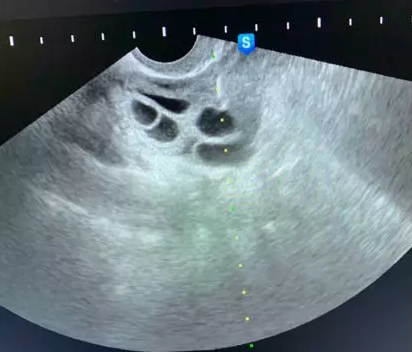

现在的取卵手术比较简单,就是在阴道超声的监护下,用一根细细长长的取卵针扎入卵泡中,通过负压吸引将卵子取出体外的技术。

卵巢位置好取卵时仅轻微疼痛

像这种情况,穿刺针进去就是卵泡,还没来得及疼呢手术就结束了!